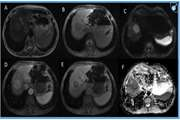

(تصویربرداری تشدید مغناطیسی) یک روش تصویربرداری پزشکی غیرتهاجمی است که برای تولید تصاویر دقیق از اندامها، بافتها و ساختارهای داخلی بدن استفاده میشود. این فناوری از میدانهای مغناطیسی قوی و امواج رادیویی برای تولید تصاویر با وضوح بالا بهره میبرد. برخلاف اشعه ایکس یا سیتیاسکن، MRI از پرتوهای یونیزان استفاده نمیکند و به همین دلیل برای بیماران ایمنتر است.

- تشخیص تومور: توسعه الگوریتمهایی برای تشخیص خودکار انواع تومورها در تصاویر رادیولوژی (مانند سیتی اسکن، امآرآی و پت اسکن).